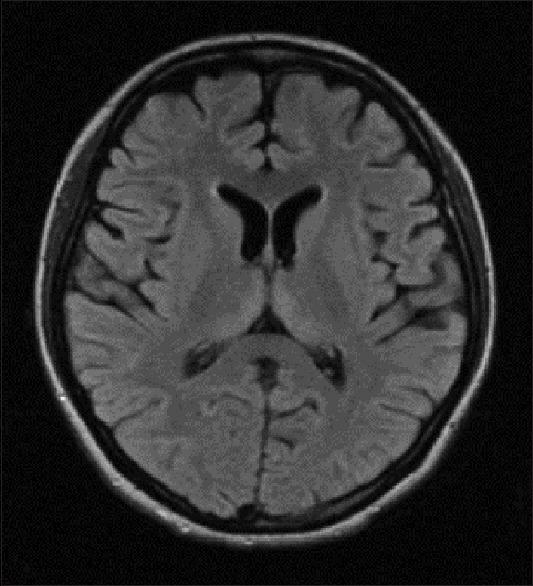

Hyperemesis gravidarum-induced Wernicke's encephalopathy (WE) is an underestimated condition. The purpose of this study is to improve its awareness and early diagnosis. We report five cases of WE secondary to hyperemesis gravidarum. Classic triad of encephalopathy, ataxia, and ocular signs was seen in four out of five patients. Two unusual features noted in this series were papilledema in one patient and severe sensory-motor peripheral neuropathy in one patient. Magnetic resonance imaging (MRI) was abnormal in all the five patients, and high signal in medial thalamus and surrounding the aqueduct was the most common abnormality (5/5). Involvement of caudate nucleus was seen in two patients with severe psychosis, and two patients had bilateral cerebellar peduncle involvement. Median time delay between onset of neurological symptoms and diagnosis was 7 days. All patients improved with thiamine, but minor sequelae were seen in four patients at 12 months follow-up. One patient had a fetal demise. Hyperemesis gravidarum-induced WE is a common cause of maternal morbidity. Typical MRI findings of symmetric medial thalamic and periaqueductal signal changes may permit a specific diagnosis. A delay in diagnosis, therefore treatment, leads to worse prognosis.

妊娠剧吐所致韦尼克脑病(WE)是一种被低估的疾病。本研究的目的是提高对其的认识并实现早期诊断。我们报告了5例继发于妊娠剧吐的韦尼克脑病病例。五分之四的患者出现了脑病、共济失调和眼部体征的典型三联征。本系列中注意到的两个不寻常特征是1例患者出现视乳头水肿,1例患者出现严重的感觉运动性周围神经病。所有5例患者的磁共振成像(MRI)均异常,内侧丘脑和导水管周围高信号是最常见的异常表现(5/5)。2例严重精神病患者出现尾状核受累,2例患者双侧小脑脚受累。神经症状出现至诊断的中位时间延迟为7天。所有患者经硫胺素治疗后均有改善,但在12个月的随访中,4例患者出现轻微后遗症。1例患者发生胎儿死亡。妊娠剧吐所致韦尼克脑病是孕产妇发病的常见原因。对称的内侧丘脑和导水管周围信号改变的典型MRI表现可能有助于做出明确诊断。诊断延迟进而导致治疗延迟会导致预后更差。